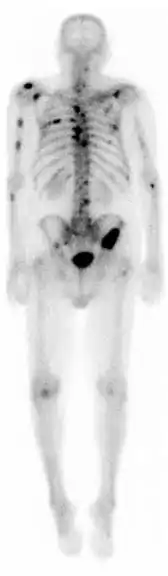

A nuclear medicine whole-body bone scan. The nuclear medicine whole-body bone scan is generally used in evaluations of various bone-related pathology, such as for bone pain, stress fracture, nonmalignant bone lesions, bone infections, or the spread of cancer to the bone.

A bone scan or bone scintigraphy /sɪnˈtɪɡrəfi/ is a nuclear medicine imaging technique of the bone. It can help diagnose a number of bone conditions, including cancer of the bone or metastasis, location of bone inflammation and fractures (that may not be visible in traditional X-ray images), and bone infection (osteomyelitis).[1]